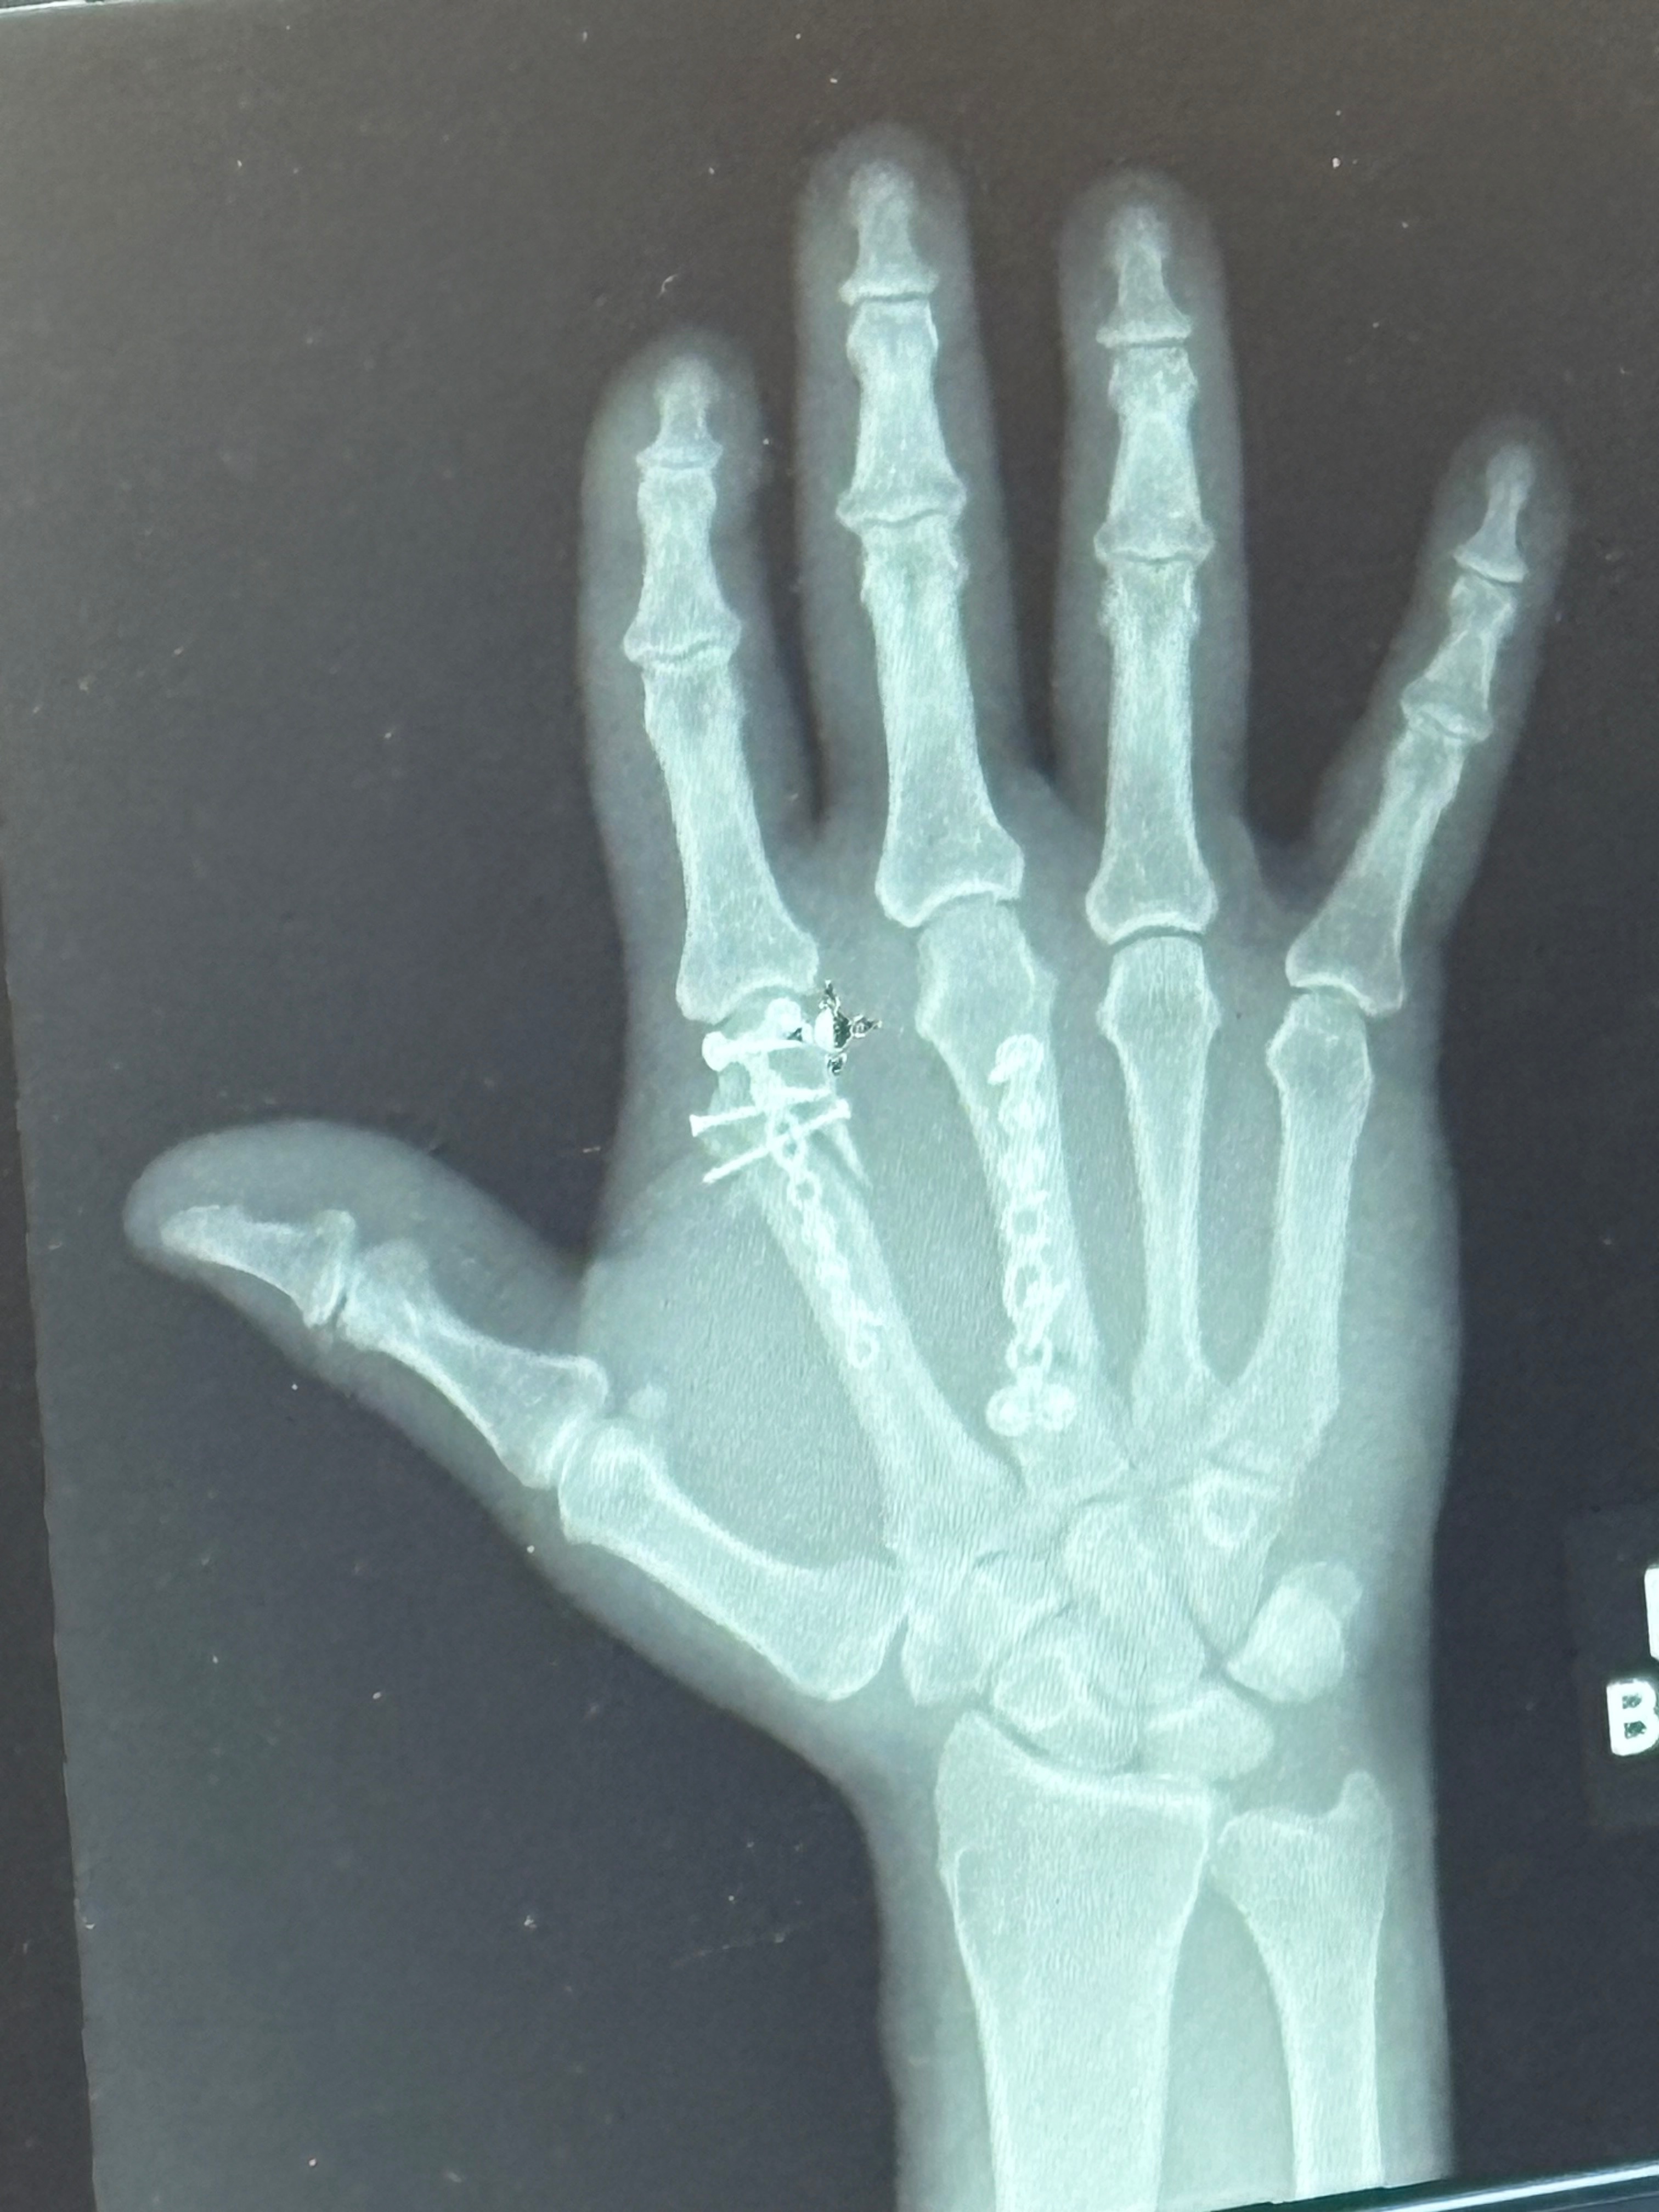

He ended up having basically an emergency surgery that night which went into the next day. He was in surgery for about 2-2 1/2 hours. He now has plates and screws in his hand. Two bones in the top of his hand were affected:

1. The bone leading up to the pointer finger were crushed in 8 places.

2. The bone leading up to the middle finger was broken in 2 places.